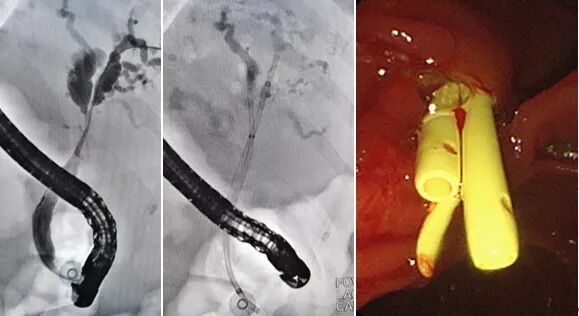

通过积极输血、输注冷沉淀及血浆改善肝功能与凝血功能后,3月6日下午,张排旗ERCP团队在介入治疗室为老人进行了ERCP+胆管支架置入术。十二指肠小乳头增加了插管难度,张排旗团队采用双导丝分别超选左右肝管成功后,置入两根胆管支架,可见黑褐色胆汁流出。陈奶奶生命体征平稳,安返病房。